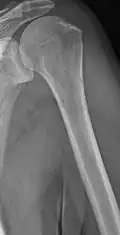

The diagnostic examination of a person with suspected multiple myeloma typically includes a skeletal survey. This is a series of X-rays of the skull, axial skeleton, and proximal long bones. Myeloma activity sometimes appears as "lytic lesions" (with local disappearance of normal bone due to resorption) or as "punched-out lesions" on the skull X-ray ("raindrop skull"). Lesions may also be sclerotic, which is seen as radiodense.[76] Overall, the radiodensity of myeloma is between −30 and 120 Hounsfield units (HU).[77] Magnetic resonance imaging is more sensitive than simple X-rays in the detection of lytic lesions. An MRI may supersede a skeletal survey, especially when vertebral disease is suspected. Occasionally, a CT scan is performed to measure the size of soft-tissue plasmacytomas. Nuclear Medicine Bone scans are typically not of any additional value in the workup of people with myeloma (no new bone formation; lytic lesions not well visualized on nuclear bone scan).

X-ray of the forearm, with lytic lesions -

Multiple myeloma in the upper arm -